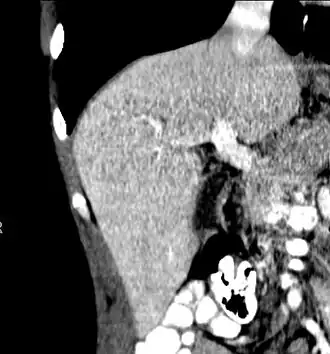

-

Axial CT image showing anomalous hepatic veins coursing on the liver's subcapsular anterior surface[74] -

Maximum intensity projection (MIP) CT image as viewed anteriorly showing the anomalous hepatic veins coursing on the anterior surface of the liver -

Lateral MIP view in the same patient as previous image -

A CT scan in which the liver and portal vein are shown